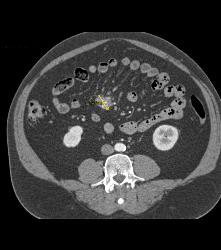

Intraductal Papillary Mucinous Neoplasm (IPMN) With Normal Small Bowel